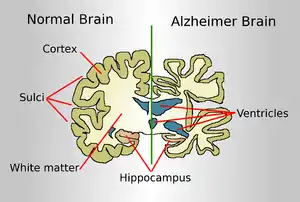

| Drawing comparing a normal aged brain (left) and the brain of a person with Alzheimer's (right). Characteristics that separate the two are pointed out. | |

Alzheimer's disease is characterised by loss of neurons and synapses in the cerebral cortex and certain subcortical regions. This loss results in gross atrophy of the affected regions, including degeneration in the temporal lobe and parietal lobe, and parts of the frontal cortex and cingulate gyrus.[93] Degeneration is also present in brainstem nuclei like the locus coeruleus.[94] Studies using MRI and PET have documented reductions in the size of specific brain regions in people with AD as they progressed from mild cognitive impairment to Alzheimer's disease, and in comparison with similar images from healthy older adults.[95][96]

Both amyloid plaques and neurofibrillary tangles are clearly visible by microscopy in brains of those afflicted by AD.[97] Plaques are dense, mostly insoluble deposits of beta-amyloid peptide and cellular material outside and around neurons. Tangles (neurofibrillary tangles) are aggregates of the microtubule-associated protein tau which has become hyperphosphorylated and accumulate inside the cells themselves. Although many older individuals develop some plaques and tangles as a consequence of ageing, the brains of people with AD have a greater number of them in specific brain regions such as the temporal lobe.[98] Lewy bodies are not rare in the brains of people with AD.[99]